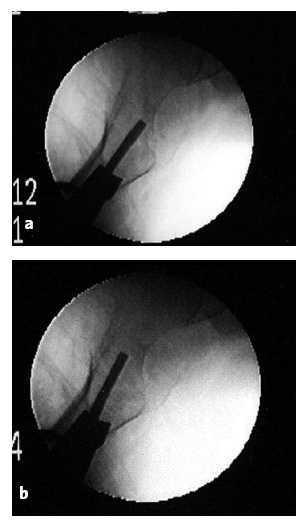

Figura 12

Inserción de los tornillos diafisarios. Los tornillos que bloquean la placa sobre la diáfisis se colocan ahora mediante la ayuda del trocar para diáfisis (nº 20) con su cánula (nº 19) sobre los orificios deseados del introductor mediante la broca (3,2 mm, nº 5). La longitud se calcula mediante la ayuda de un medidor (nº 21).

Los tronillos se insertan mediante la ayuda de motor).

Después de la inserción del primer tornillo de diáfisis, la placa está sujeta al hueso por un tornillo de cuello y uno de diáfisis. Ambos tornillos previenen que la placa se desplace de la diáfisis y ahora podemos retirar la pinza reductora así como el pin de fijación al trocánter. El pin de trocánter se retira fácilmente con la ayuda de motor. Para retirar la pinza reductora el primer paso es retirar el adaptador (nº 18). Posteriormente tirar del mango distal (MD) y girar ambos brazos 90º. De esta manera aflojamos la presa sobre el fémur. Retiramos ambos brazos gradualmente. Posteriormente colocamos un segundo y tercer tornillos diafisarios de la misma manera que el primer tornillo de diáfisis.